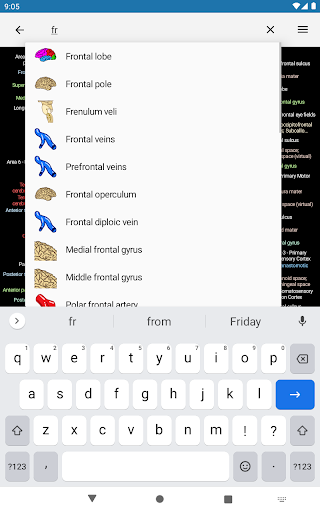

* تحسين أداء البحث عن البنية التشريحية

* اعثر على الأجزاء التشريحية الخاصة بك بسهولة أكبر بفضل ميزة البحث الجديدة والأكثر سهولة وقوة